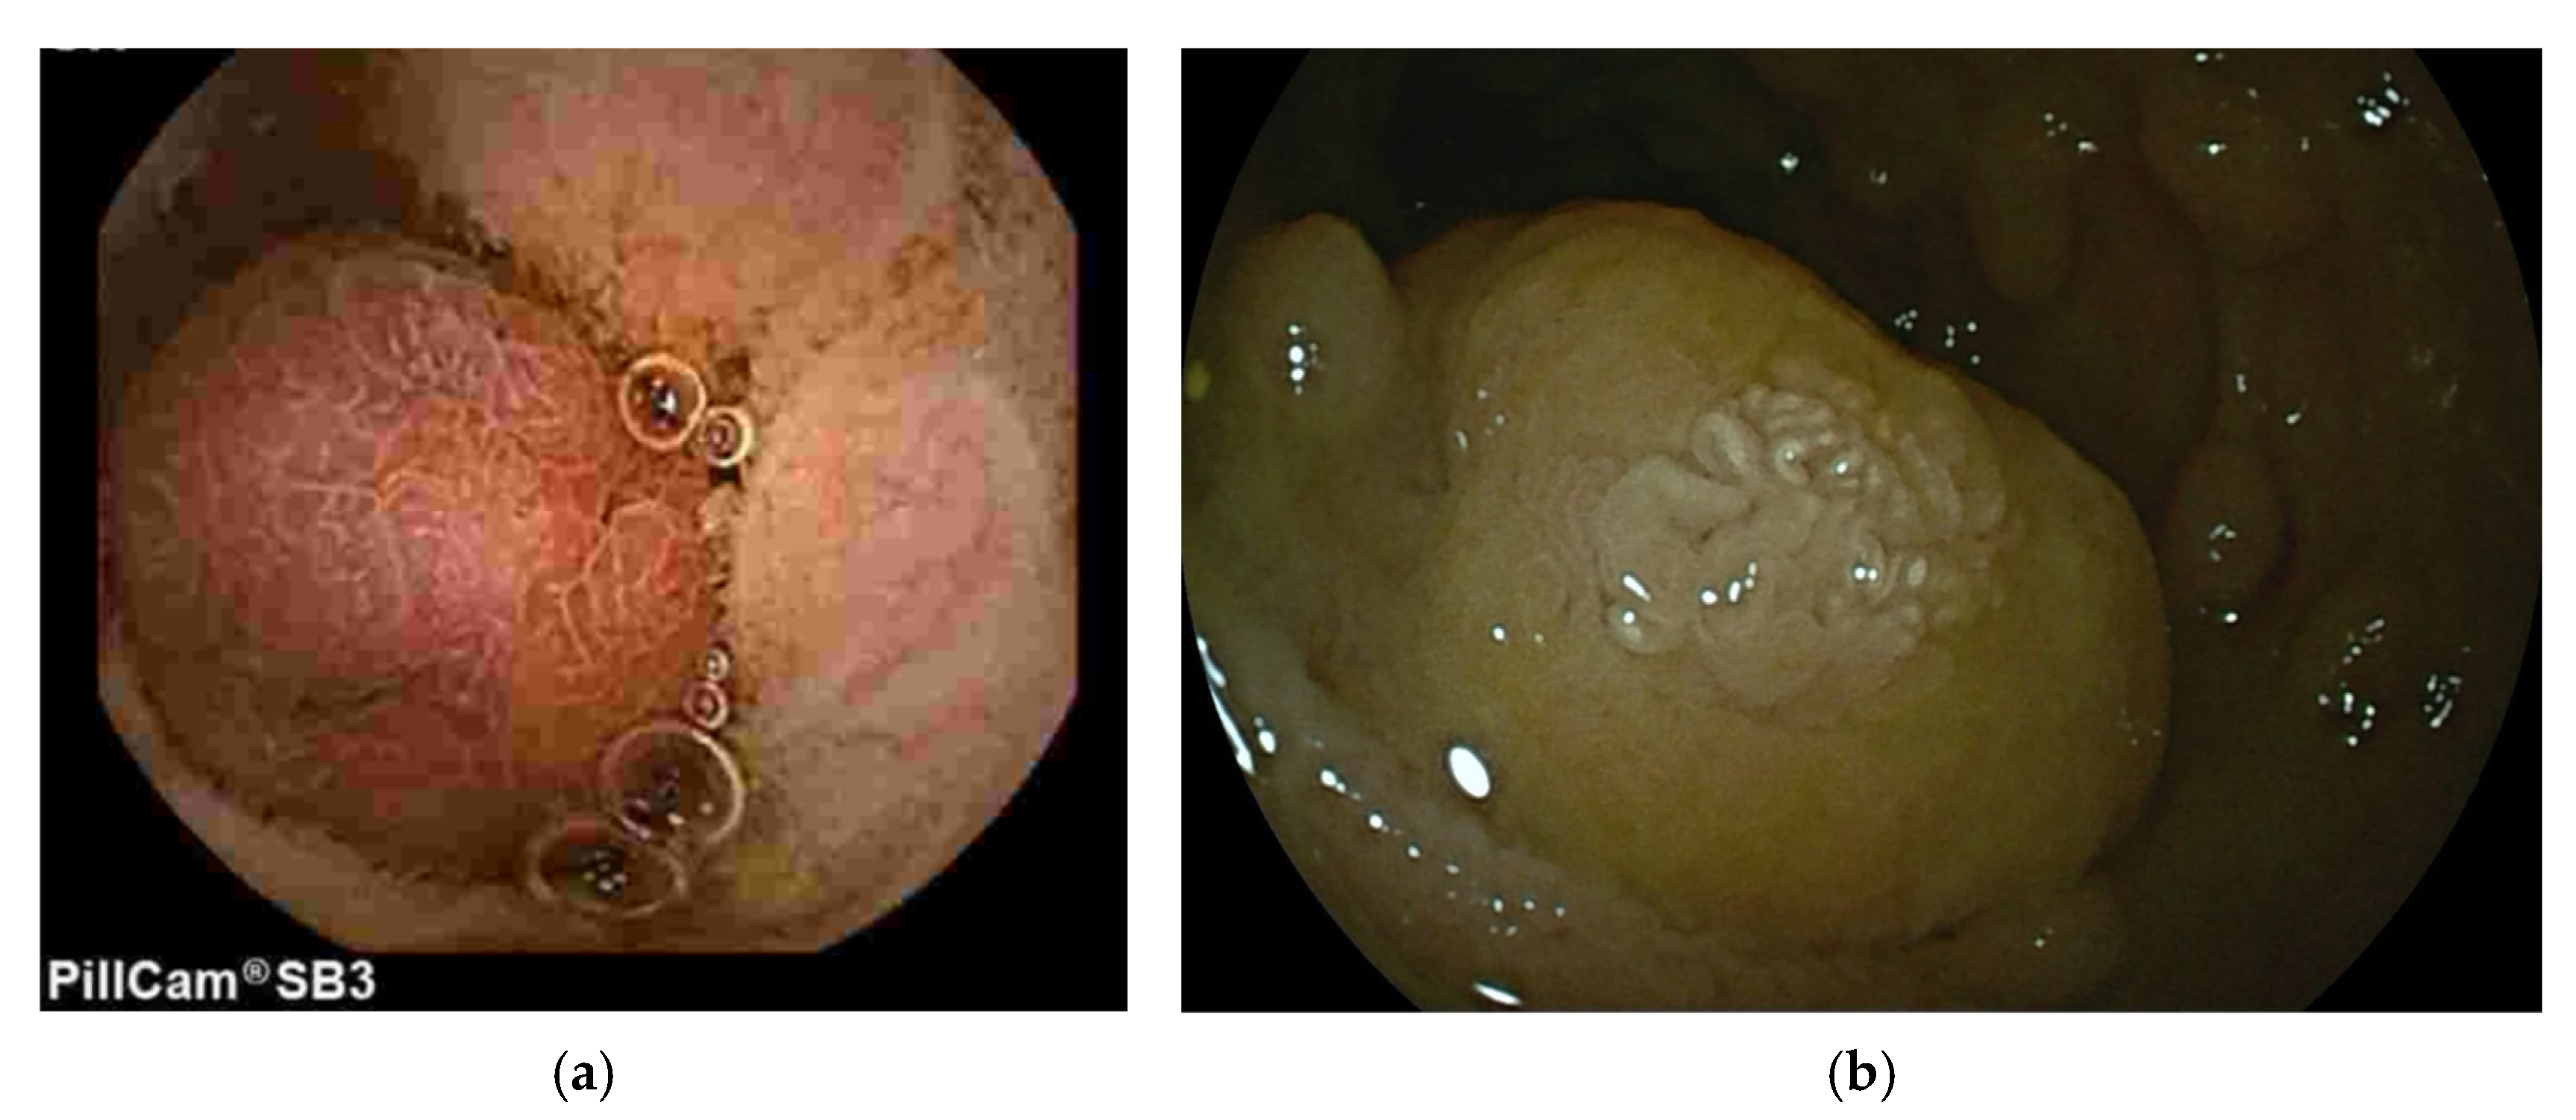

3.1. Peutz-Jeghers Syndrome (PJS)